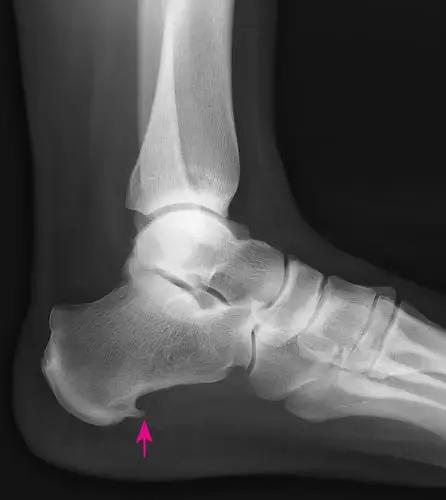

跟骨骨刺

骨刺是骨骼上的异常骨增生,常常发生在关节或骨头结合处,可能导致疼痛